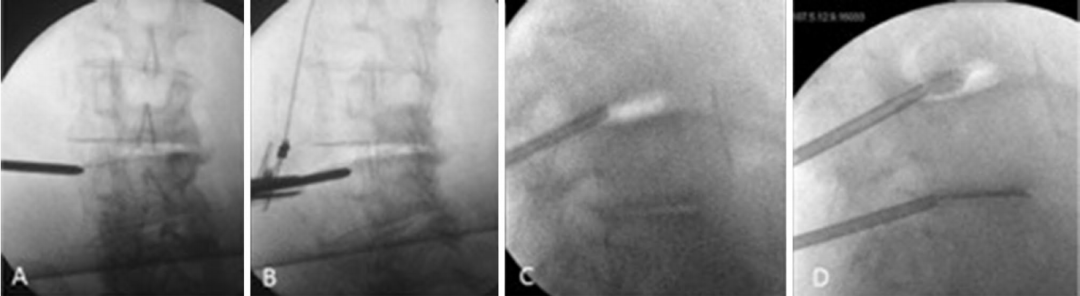

图: PCD术中图像a: 向椎间盘间隙插入Jamshidi 针; b: 针在正位时的位置; c,d: 将K-wire 插入Jamshidi针内; e,f: 插入椎体成形术套管针; g,h:PMMA骨水泥填充椎间盘; i,j: 术后情况

图: A: 俯卧位,髋关节伸展,以增加腰椎前凸和椎间盘间隙; B: 经皮透视下放置Jamshidi针; C: 在肌电图监护下穿刺并注射; D: 缓慢注射骨水泥